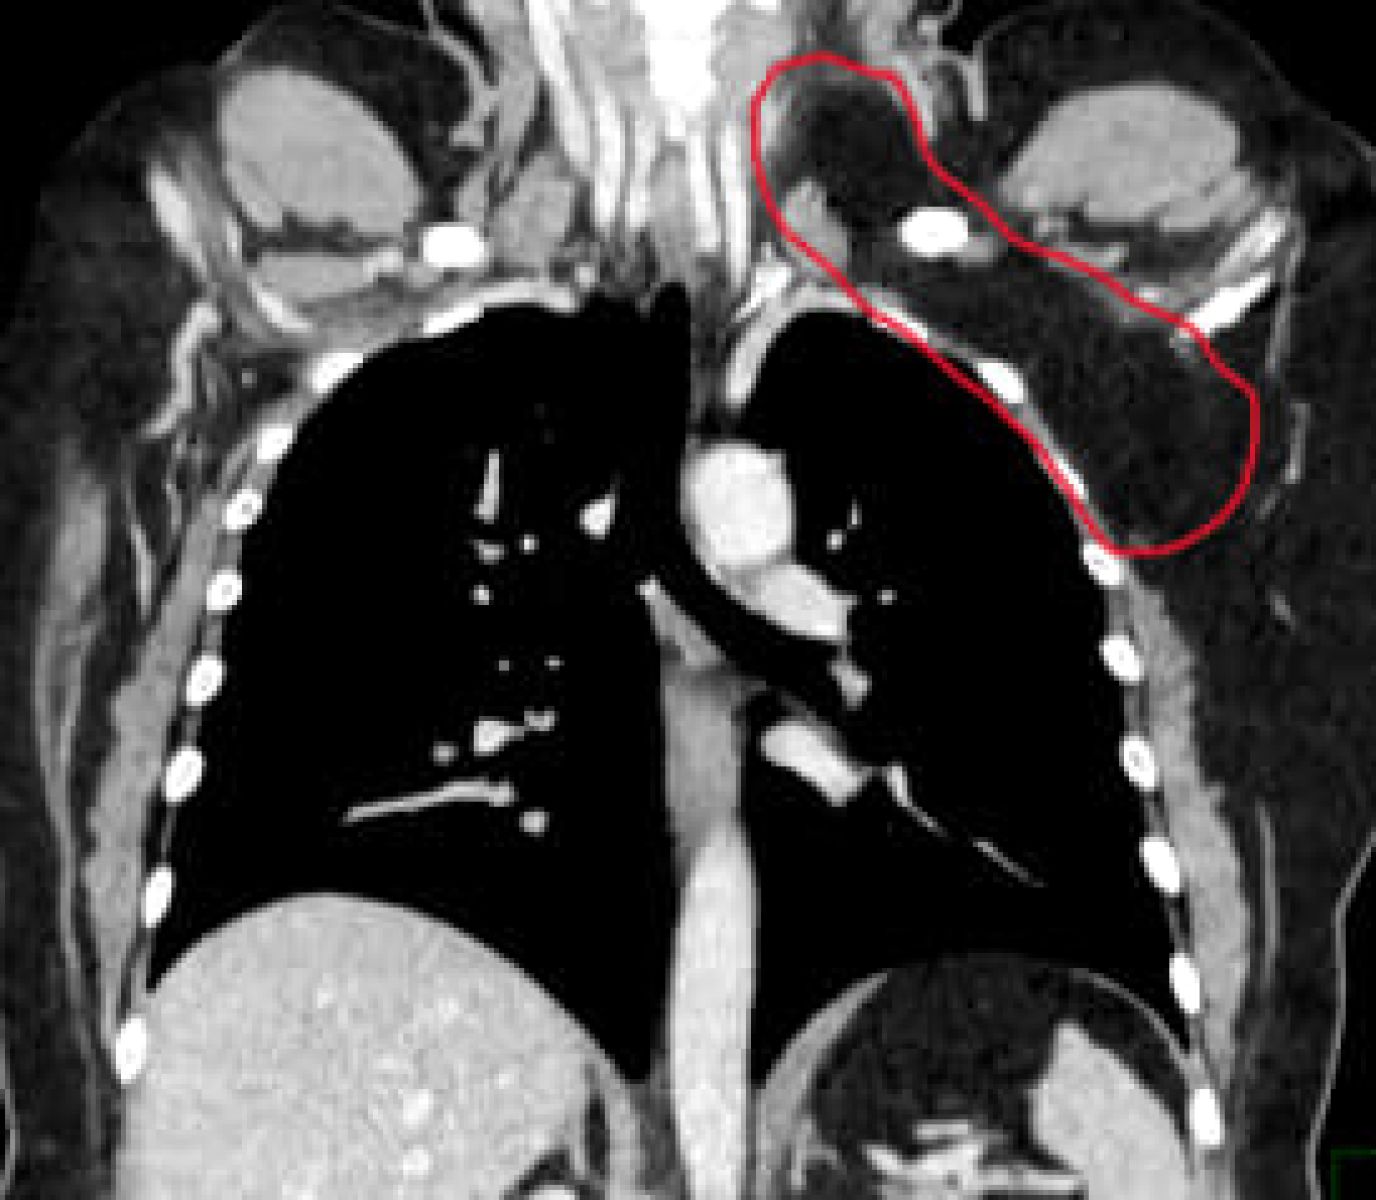

Опухоль размером с дыню, 20 х 15 сантиметров, удалили воронежанке, сообщил региональный Минздрав.

50-летняя женщина обратилась к медикам в онкоцентр, когда заметила новообразование в области левой надключичной ямки. Опухоль начала расти и доставляла дискомфорт.

Сначала горожанке поставили страшный диагноз — рак, липосаркома. К счастью, при дальнейших исследованиях вердикт не подтвердился. Выяснилось, что опухоль доброкачественная, липома. Она формируется из патологически разрастающейся жировой ткани.

Новообразование занимало две области организма, надключичную и грудную, а также окутывала жизненно-важные структуры. Команда медиков во главе с кандидатом медцинских наук Михаилом Фонштейном провела сложную операцию и вырезала опухоль.